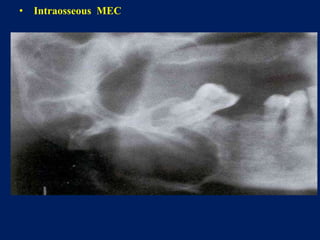

• Intraosseous MEC

• Low grade